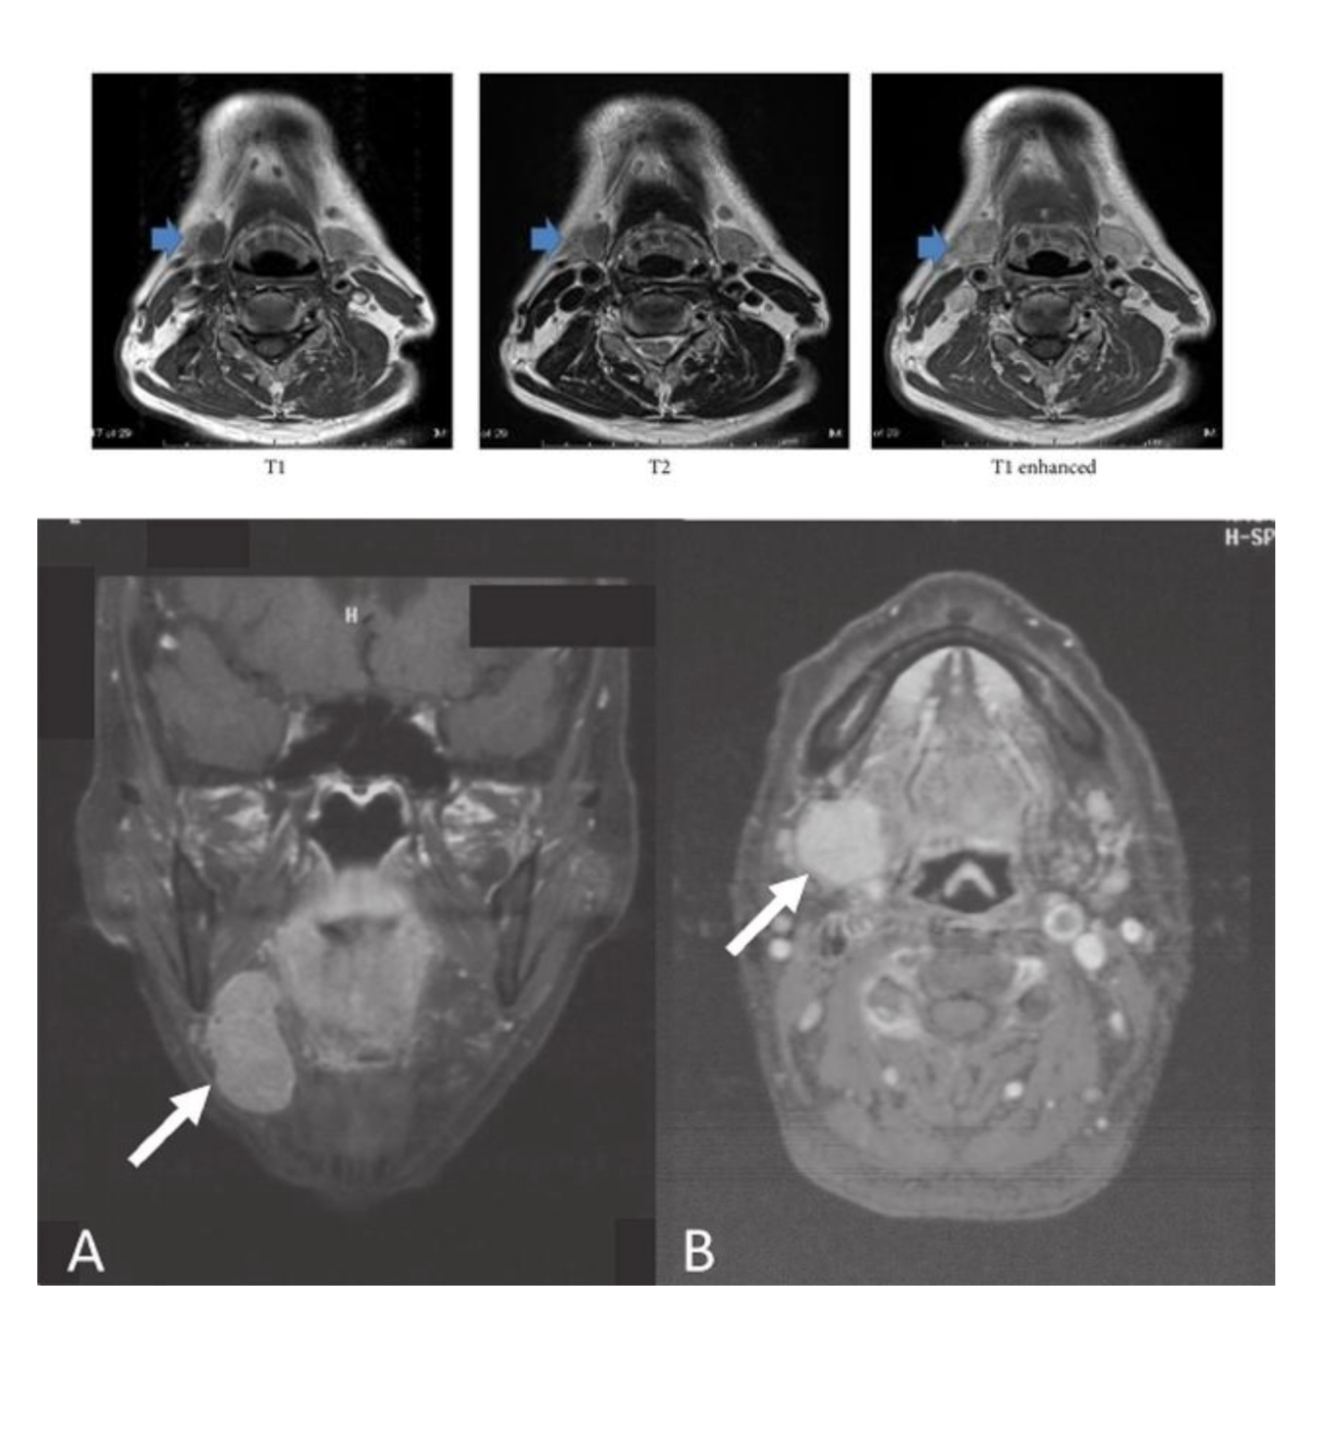

What does arrow indicate?

A

left parotid mass

Q

What does arrow indicate ?

submandibular gland

Vocal cord Schwannoma